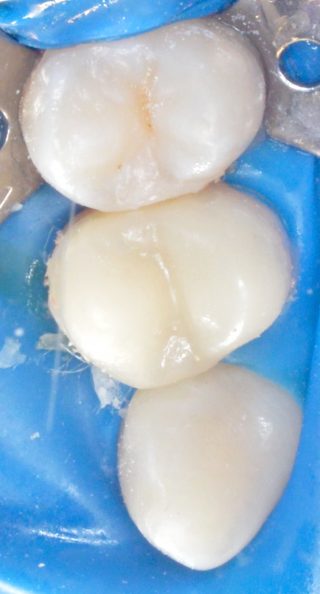

S-a pastrat in intregime smaltul sanatos pentru a avea o adeziune optima, am luat amprenta dintelui restant, iar apoi, in laboratorul de tehnica dentara s-a realizat coroana partiala din material compozit. Coroana partiala a fost cimentata pe dinte, rezultatul estetic fiind unul de exceptie datorita integrarii coloristice pe care materialele fizionomice le pot oferi.

Pentru cele mai bune rezultate in prevenirea fracturilor in urma tratamentului endodontic se folosesc coroane partiale cu protectie cuspidiana sau coroane totale.

In cazut molarilor/premolarilor care prezinta leziuni mezio-ocluzo-distale riscul de fractura de este foarte ridicat datorita desfiintari crestelor marginale de smalt, zone care oferta rezistanta dintelor. Studiile arata ca odata desfiinte aceste creste apare un grad forte mare de flexie la nivelul cuspiziilor (varfurile molarilor/premolarilor), iar cu cat cavitatea este mai profunda, ca in cazul dintilor tratati endodontic, lungimea cuspizilor creste ducand la o rata de flexie egala cu cubul lungimii. In astfel de situatii o restaurare directa din compozit (plomba) este de cele mai multe ori contraindicata deoarece fortele nu sunt distribuite in mod egal pe suprafata dintelui (fig1.) Protectia cuspidiana exact acest lucru in ofera, o distributie egala in axul lung al dintelui a fortelor ocluzare (fig2.) Avantajul coroanelor partiale cu protectie cuspidiana compartiv cu o coroana de invelis totala este faptul ce dintele necesita o reducere a structurii sale cu 50% mai scazuta. Noile tehnici adezive fac posibila pastrarea a cat mai mult din dinte.